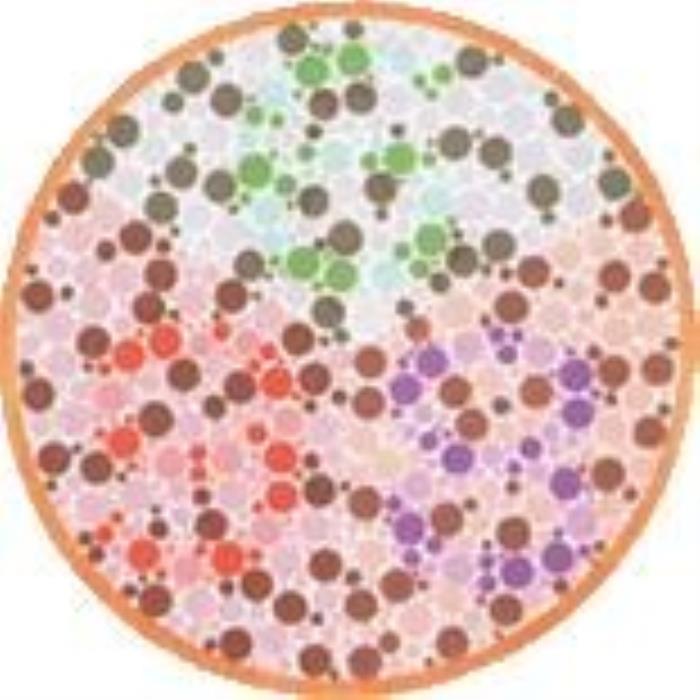

·数字图1

结果:正常看到的是66,看不出是红绿色盲

·数字图2

结果:正常看到的是698

·数字图3

结果:正常看到的是6,看不出是绿色盲

·数字图4

结果:正常看到的是29

·数字图5

结果:正常看到的是812

·数字图6

结果:正常看到的是628